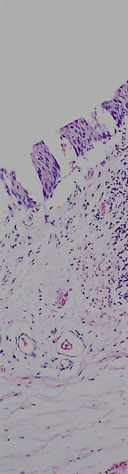

The mucosa is irregularly separating from the underlying submucosa due to post mortem autolysis.